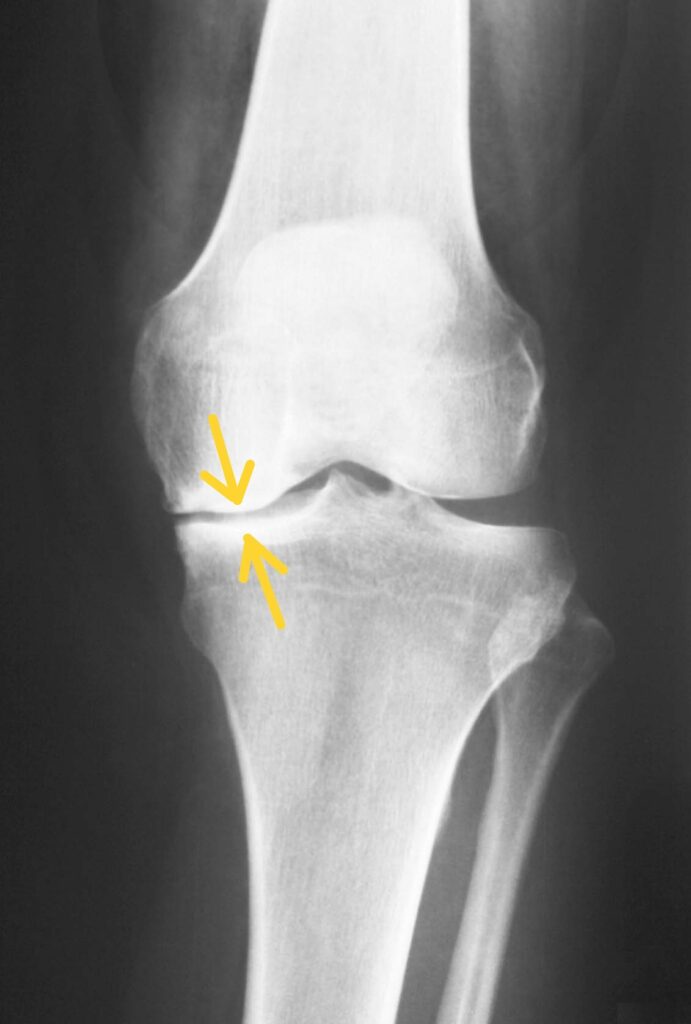

Pangonarthrose: Bei dieser schwerwiegendsten Form sind alle Gelenkkompartimente vom Verschleiß betroffen. Die Symptome sind entsprechend ausgeprägter und die Behandlung komplexer.

Röntgenbild einer schwerwiegenden Arthrose im Kniegelenk mit nahezu aufgebrauchten Gelenkspalt innen- und außenseitig (Pangonarthrose)